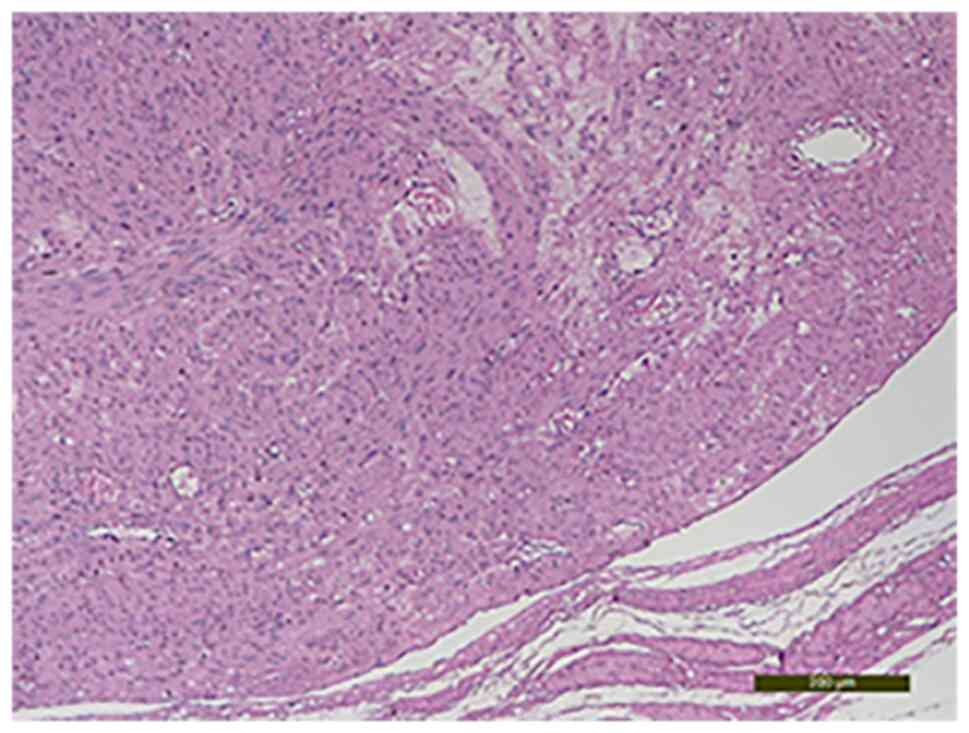

The histological examination with hematoxylin-eosin staining showed fusiform cells that had moderate nuclear atypia, rare mitosis, areas of sclerosis and hyalinosis, interstitial edema and degenerative modifications. The specimen was processed according to standard histological technique and the slides were stained with the conventional hematoxylin and eosin staining (HE) method (7). Briefly, the uterine mass tissues was fixed in formaldehyde (neutral buffered formalin 10%) for 24 h at room temperature (24˚C) and then the specimen was dehydrated in alcohol, cleared in xylene and embedded in paraffin. Clarification was achieved by passing the fragments through three xylene baths to remove alcohol from the tissues, for 4-6 h. The impregnation with paraffin was achieved by placing the tissue fragments in three paraffin baths for a minimum of 24 h at a temperature of 56˚C. The slides obtained were placed in a thermostat at 58˚C for 24 h and later stained using HE staining. The paraffin blocks were sectioned at 4 µm. The tumor with intravascular growth featured uniform spindle-shaped smooth muscle cells (Fig. 5, Fig. 6 and Fig. 7). Also, the presence of adenomyosis was confirmed. This diagnosis was not suspected prior to the surgery and it was an unusual histopathological finding.

Figure 6

Intraluminal growth of dense cellular proliferation with uniform spindle-shaped smooth muscle cells in the venous channels of the myometrium (hematoxylin-eosin staining; magnification, x10).